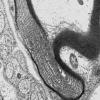

PERIPHERAL NEUROPATHY